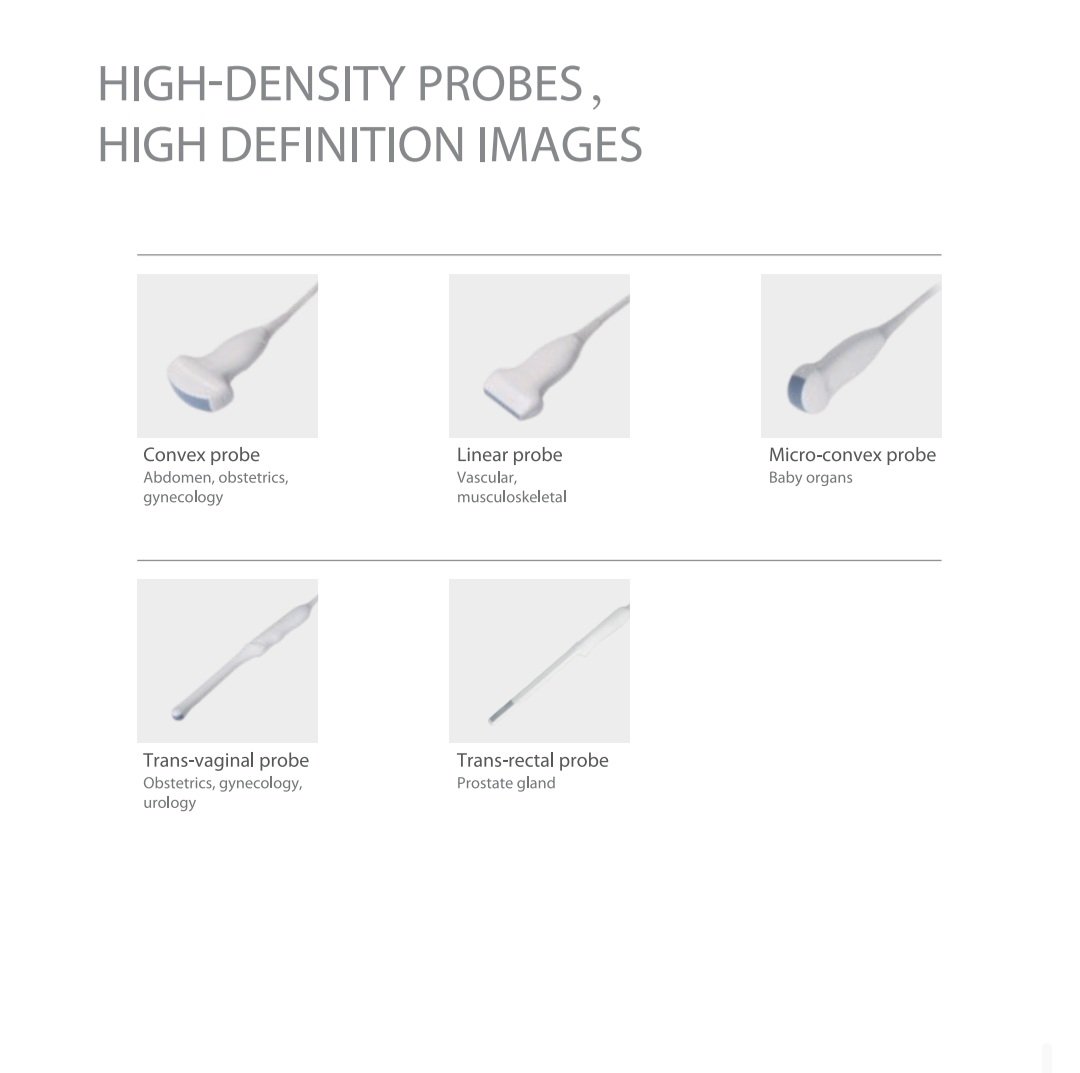

🩻 High-Density Probes for Superior Image Quality

This diagnostic ultrasound supports a range of high-density probes, each optimized for specific medical fields.

Available Probe Types:

-

Convex Probe: For abdomen, obstetrics, and gynecology applications.

-

Linear Probe: For vascular and musculoskeletal imaging.

-

Micro-convex Probe: Ideal for pediatrics and small organ imaging.

-

Transvaginal Probe: For gynecology, obstetrics, and urology examinations.

-

Transrectal Probe: For prostate and rectal imaging.

All probes deliver high-resolution, clear, and consistent images, ensuring diagnostic accuracy in every scan.